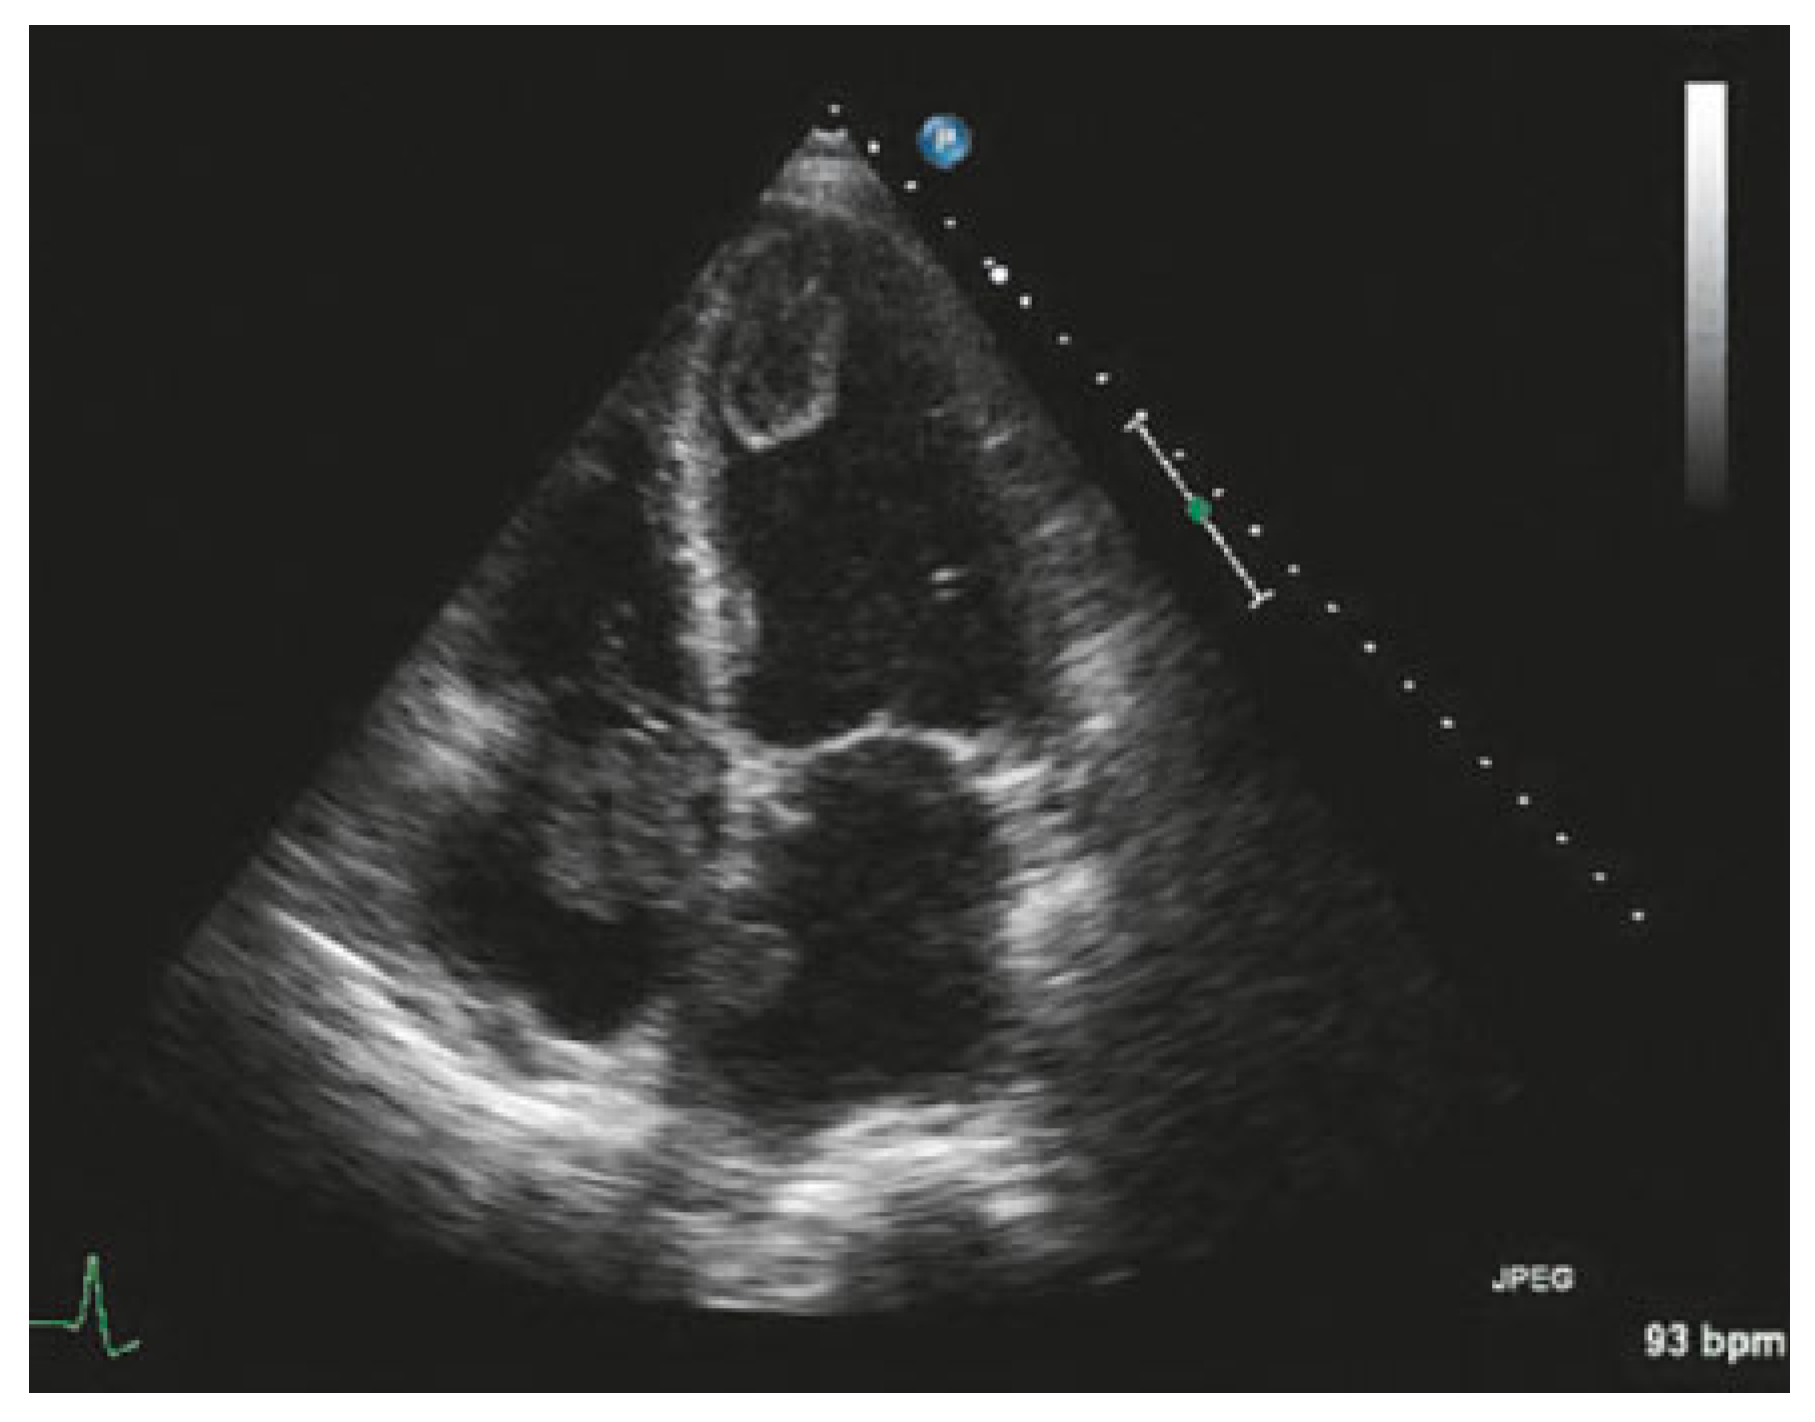

According to the current ESC guidelines for patients with non-ST elevation myocardial infarction (NSTEMI), echocardiography is recommended for evaluating global and regional leh ventricular function, as well as for assessing differential diagnoses; it should be performed urgently in all patients with haemodynamic instability [

26]. Echocardiography is also very useful for investigating complications of myocardial infarction when an acute coronary syndrome is suspected (

Figure 2).